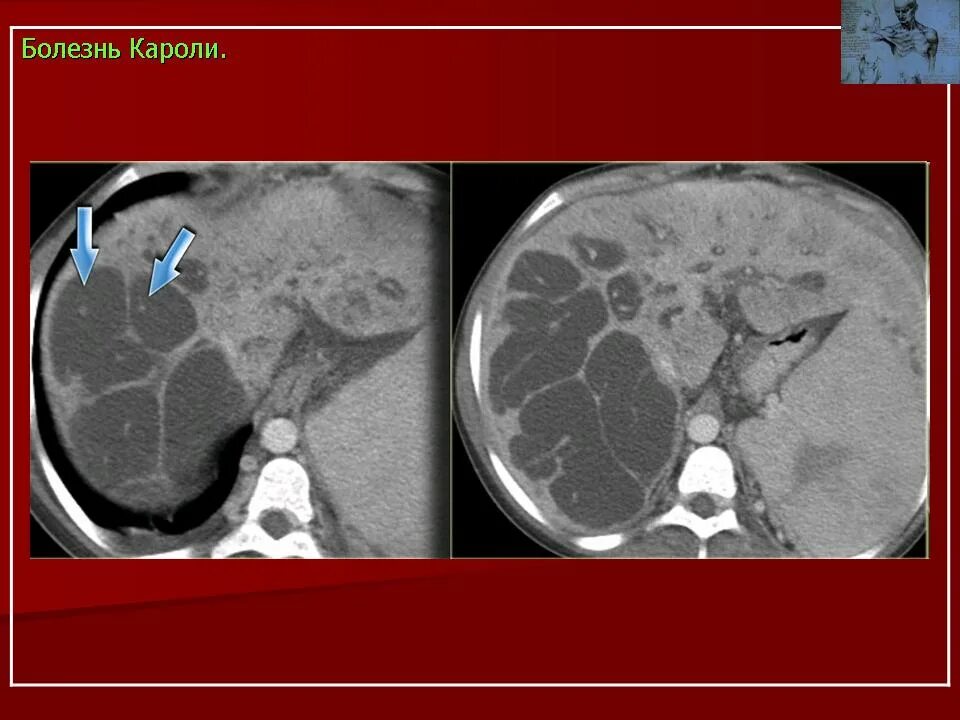

Заболевание кт